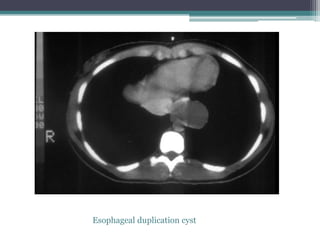

โ–ซ Single slice from an enhanced chest CT exam shows the mass to be

non-enhancing, posterior to the right bronchi, and next to the

esophagus.

โ–ซ Dx: Esophageal Duplication

Esophageal duplication cyst